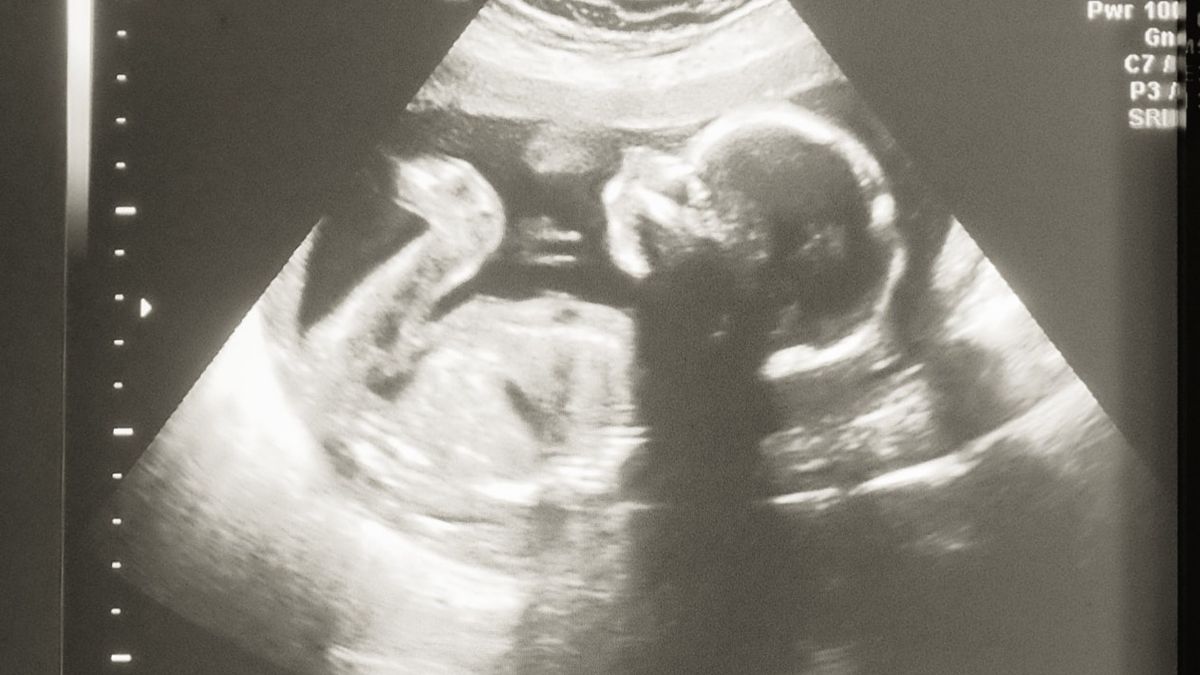

Na 18 weken zwangerschap breken mijn vliezen. De bloedingen die ik al die weken heb gehad, hebben voor een zwakke plek in mijn vliezen gezorgd, waardoor er een scheur in kwam. Ik word doorgestuurd naar de gynaecoloog. Ze maken ook daar weer een echo en een CTG om weeënactiviteit te meten. Er zijn geen weeën te bespeuren, en ik word naar huis gestuurd met de woorden dat het nu vanzelf op gang zou komen. Vruchtwater vult zichzelf weer aan, maar ook bij bijna elke beweging die ik maak lekt het weer weg. Er breekt een tijd aan van elke dag naar het ziekenhuis gaan. Elke dag wordt er een echo gemaakt. Tot er op een gegeven moment een gynaecoloog zegt dat het haar verbaast dat ze elke keer nog een krachtig kloppend hartje ziet. Ik moet het zien uit te zingen tot 24 weken, daar voor doen ze eigenlijk geen moeite om een baby in leven te houden. Ook krijgen we te horen dat mocht onze baby het redden tot 24 weken, hij waarschijnlijk niet gezond ter wereld komt. Dit omdat mijn vliezen zijn gebroken, maar de baby het vruchtwater nodig heeft om de longen te laten rijpen en om in te bewegen. We zouden dus niet weten of de spieren en gewrichten allemaal goed ontwikkelen.

28 april 2013, mijn broer is jarig, maar ik ga niet mee. Mijn vriend gaat er heen met de kinderen, en ik ga op bed liggen, want ik voel me niet lekker. Op een gegeven moment merk ik dat er weeën op gang komen. Ik ben dan 19.5 weken zwanger. Mijn vriend komt naar huis, maar laat de kinderen achter bij mijn moeder. Ik moet mij melden op de verlosafdeling van het ziekenhuis, en mijn vriend gaat natuurlijk mee. Mijn buurvrouw en tevens vriendin zet ons af, wij gaan naar binnen. Ik moet zoals verwacht blijven en ik mag in een aparte kamer gaan liggen. Hier komt bij elke beweging die ik maak bloed vrij. Tot er op een gegeven moment een heel groot stolsel vrij komt, die eruit geduwd moet worden. Er wordt door de verpleging zo hard op mijn buik geduwd dat ik het uitschreeuw van de pijn. De gynaecoloog komt om een echo te maken, het stolsel was zo groot dat het een liter bloed bevatte en ze wil kijken hoe het met de baby gaat. Het hartje klopt nog steeds krachtig, en de baby beweegt ook nog steeds. Ze gaat in gesprek met mijn vriend, ze zegt hem dat hij op dit moment geen keus meer kan maken of ze de baby nog proberen te redden. Hij is nu nog niet levensvatbaar dus de keus is gemaakt en ze kiezen voor de moeder. Ze besluiten om de baby nu meteen te halen, en mij naar de OK te brengen. Ik kan nog net afscheid nemen van mijn vriend en zeggen dat hij iemand moet bellen om hem bij te staan. Ik wil niet dat hij dit alleen doet. Hij belt mijn vriendin op en die komt er meteen aan. Het is inmiddels half 1 ’s nachts. Eenmaal op de OK aangekomen willen de doktoren mij klaarmaken, maar ik blijk geen ontsluiting te hebben en ze brengen mij naar de IC. Mijn lichaam moet het zelf doen. Op de IC is er alleen nog plek op de zaal. Ze halen een oudere man uit een aparte kamer om plaats te maken voor mij. Mijn vriend en vriendin worden opgehaald en ze mogen bij mij blijven. Vanaf dit moment wordt alles wazig voor mij. Ik verlies veel bloed, ik krijg bij elkaar zes infusen in mijn armen en er moet een slagaderinfuus aangelegd worden. Hiervoor moeten ze een arts oproepen, die niet aanwezig is in het ziekenhuis. Mijn vriend en vriendin worden naar de gang gestuurd, omdat er een katheter ingebracht moet worden. Er wordt ze verteld dat het vijf minuten zou duren, maar ondertussen komt de arts binnen die het slagaderinfuus komt aanleggen. Omdat er geen ruimte meer is in mijn armen, wordt deze in mijn voet geprikt. Eerst mijn rechter voet, wat niet lukt, daarna in mijn linker voet. Ik krijg het vaag mee. Mijn vriend staat nog steeds op de gang en heeft er ondertussen de beveiliging bij staan omdat hij flipt. Het zou maar vijf minuten duren, ondertussen zijn we driekwartier verder. Ze mogen na het aanleggen van het infuus in mijn voet weer naar binnen, maar ik krijg het bijna niet mee. Mijn bloeddruk is ondertussen gezakt naar 21/17. Er worden nog steeds echo’s gemaakt, onze baby houd nog steeds vol en laat nog steeds een kloppend hartje zien. Ik zak steeds verder weg door het bloedverlies. Ik krijg amper nog de weeën mee. Onze baby moet NU gehaald worden. Met een team van zes mensen drukken ze keihard op mijn buik en ik voel mijn baby naar buiten glijden. Op 29 april 2013 rond 4.15 uur wordt onze zoon geboren. We noemen hem Cayden, wat vechter betekent. Vlak voordat hij geboren wordt, is hij door alle medicatie die ik kreeg direct overleden. Er was verder niks mis met hem, mijn lichaam kon de zwangerschap niet aan. Cayden is in besloten kring gecremeerd en zijn urn staat nu bij ons thuis. Ook draag ik een hanger met zijn as. Ik was 19 weken en 6 dagen zwanger en uitgerekend op 17 september 2013. Op 17 september 2014, precies een jaar na zijn uitgerekende datum, kreeg ik te horen dat ik de volgende dag zou worden ingeleid voor de geboorte van zijn zusje, ons regenboogkindje.